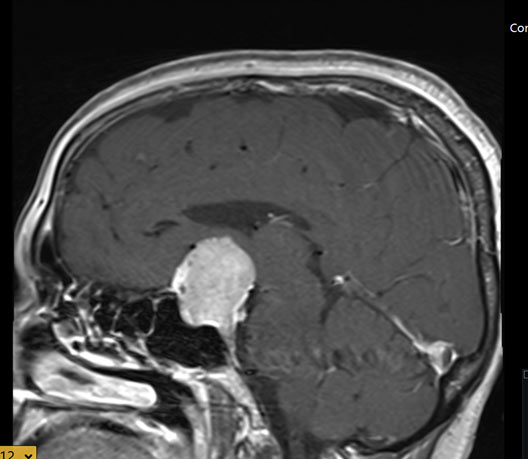

בן 45 עם מאקרואדנומה היפופיזרית, לא מפרישה אשר התגלתה בעיקבות הפרעת ראיה, אשר נותח להסרה בגישה אנדוסקופית טרנס ספנוידלית